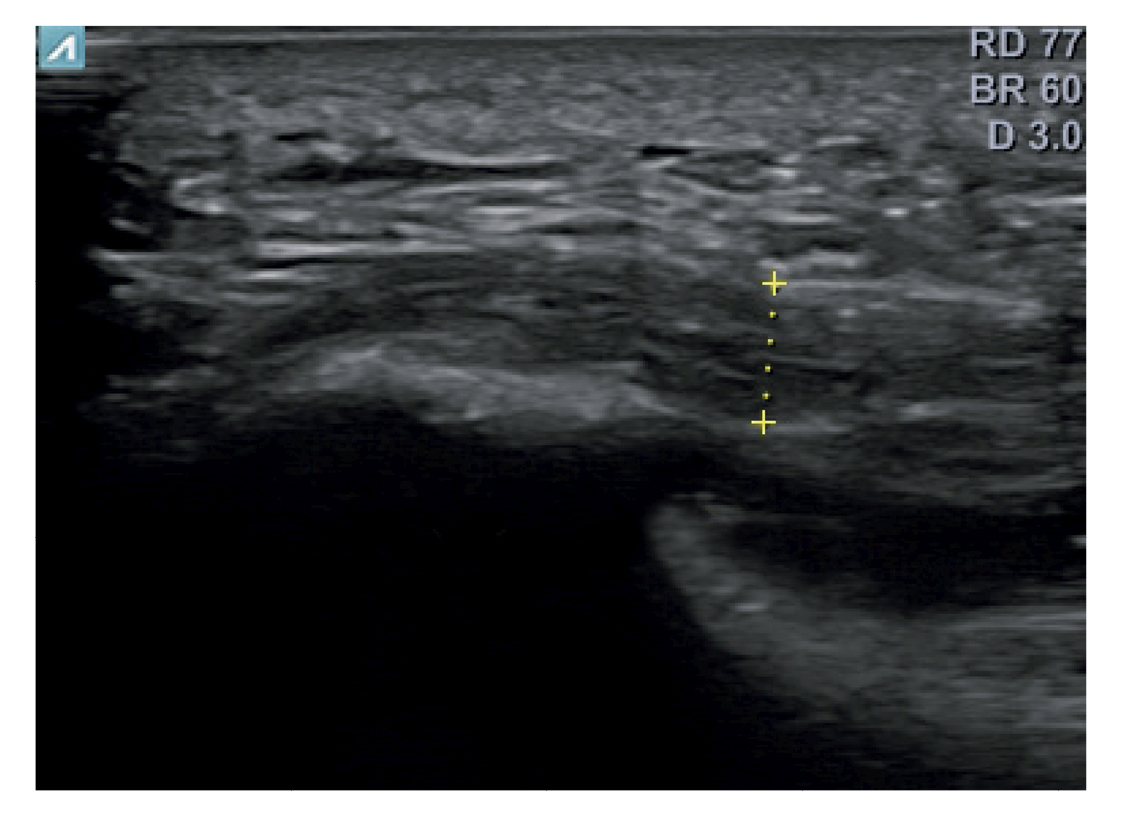

All patients had experienced the classic symptoms of PF, including pain when taking the first steps after waking up or after sitting for a long time. Patients felt pain upon palpation of the proximal plantar fascia and reported that the pain worsened as the day progressed. The diagnosis was established based on symptoms and confirmed by ultrasound using high-resolution equipment (Alpinion Ecube 9, ALPINION MEDICAL SYSTEMS Co., Ltd., Republic of Korea) with a 6-12 MHz linear transducer (Figures 2 and 3).

Figure 3. Area of measurement of plantar fascia thickness. The dotted line corresponds to the thickness measurement.